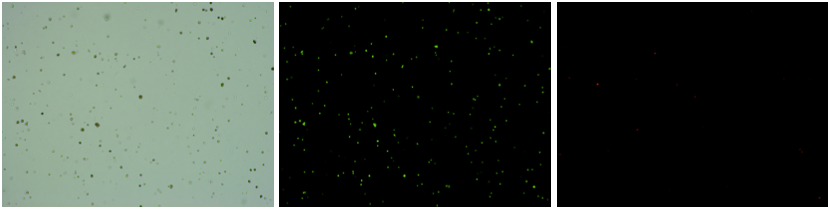

人腎癌樣本,細(xì)胞活率:94.69%,結(jié)團(tuán)率:6.6%